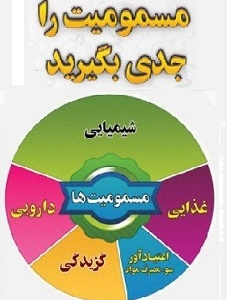

هفته پیشگیری از مسمومیت

۰۱ آبان ۱۴۰۳هفته پیشگیری از مسمومیت از 1 تا 7 آبان می باشد که در این هفته تمرکز به صورت کشوری، بر ...